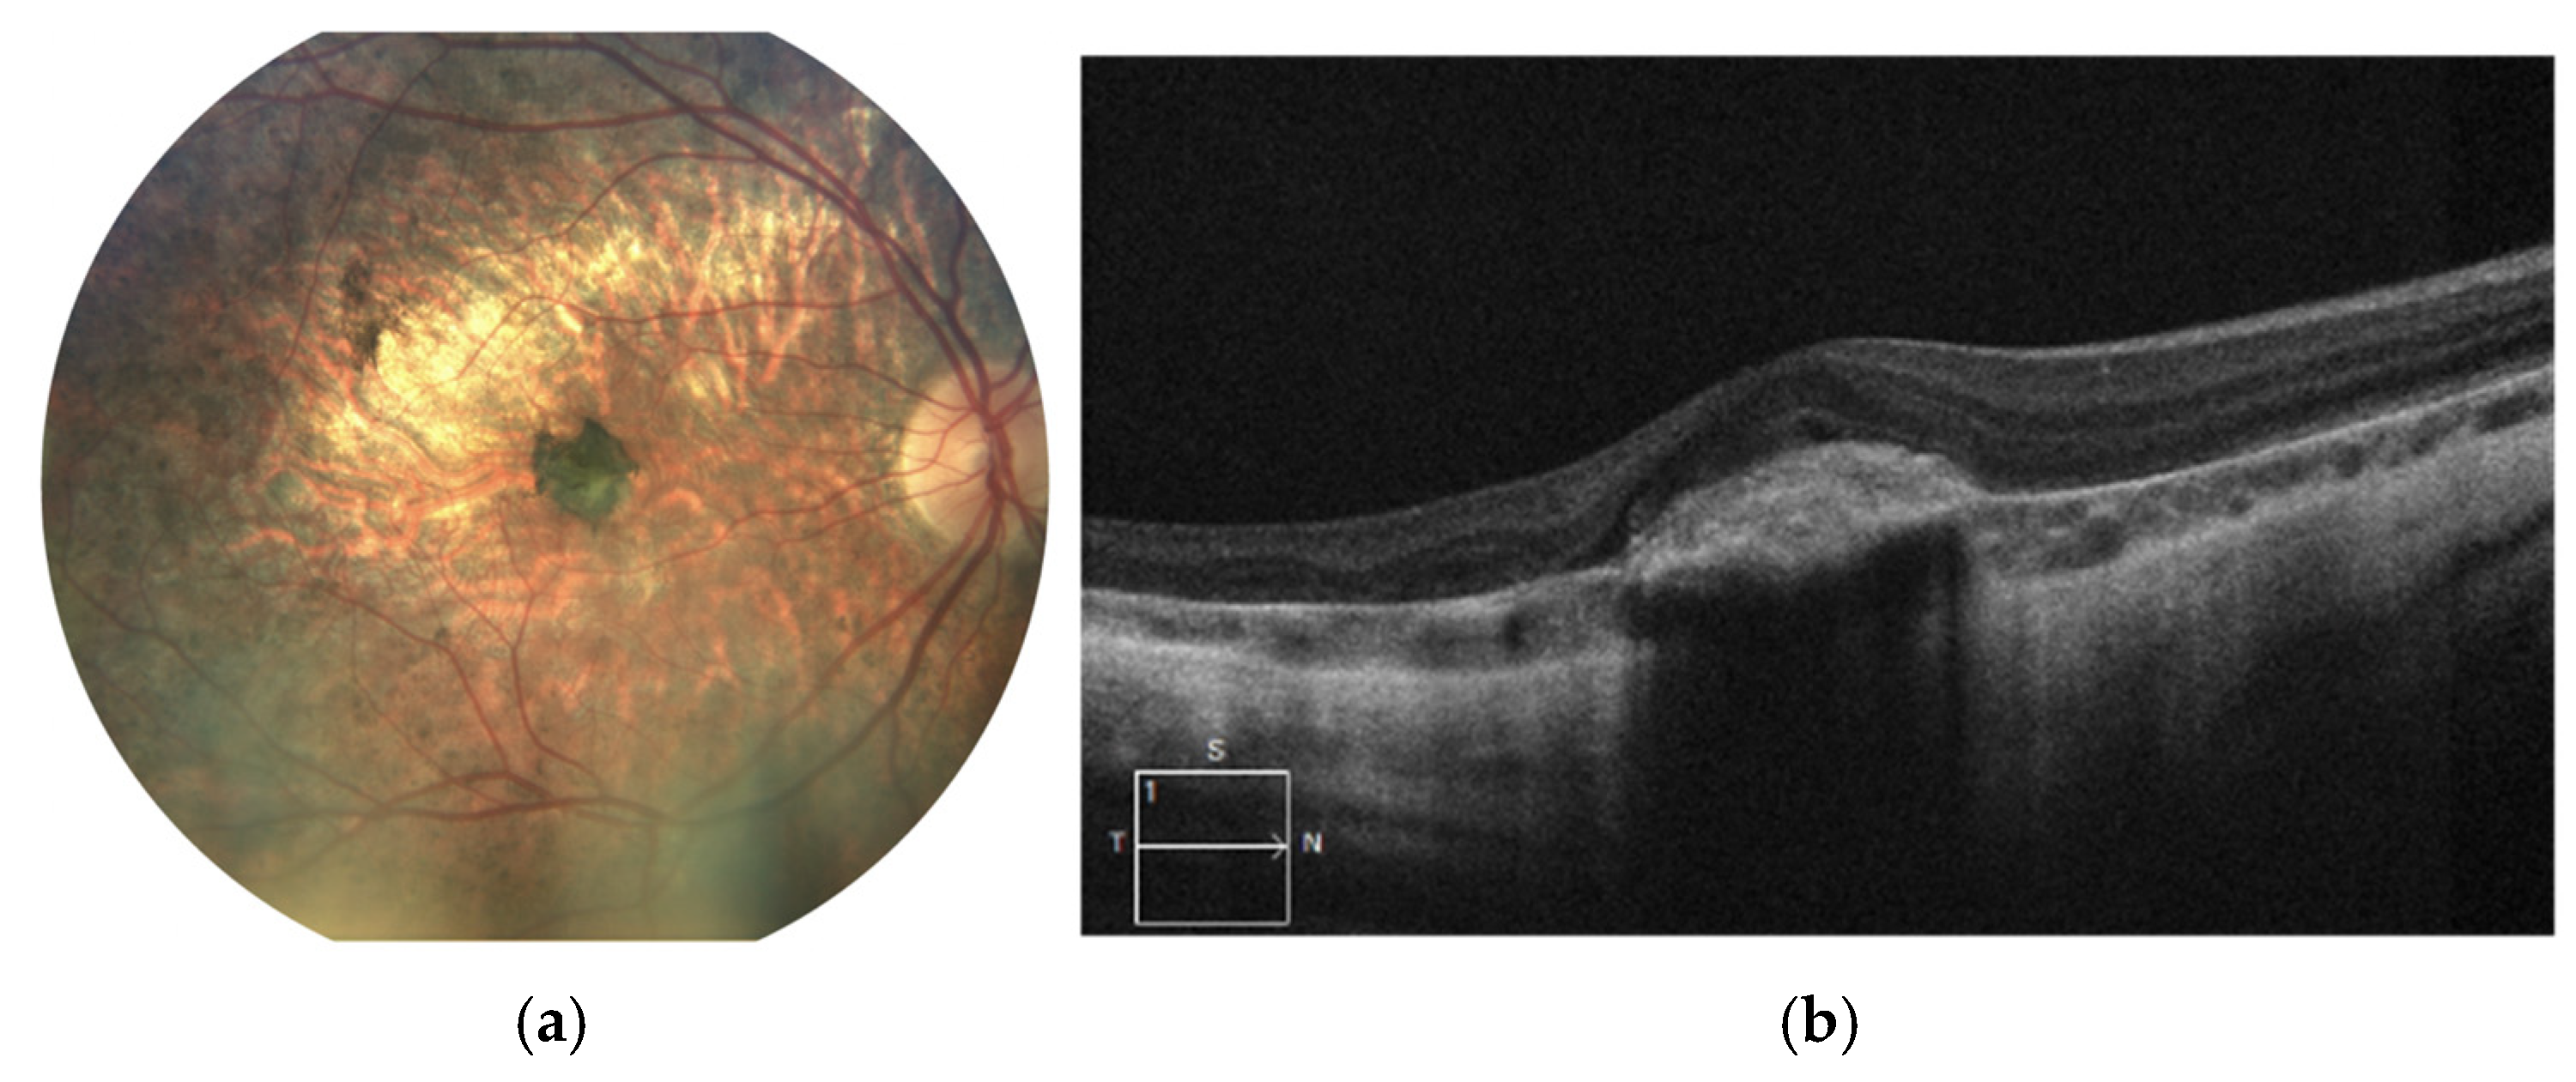

The latest fundus images and SD-OCT scans of the right eye are shown in Figure 3a,b. The images demonstrate progressive atrophy of the retinal pigment epithelium (RPE) and the choroid in the posterior pole followed by development of staphyloma. Pigmentary changes following MNV remain stable.

Figure 3. Images of the right eye: (a) color fundus photograph and (b) SD-OCT scan. Marked chorioretinal atrophy is visible in the posterior pole, accompanied by a large pigment clump consistent with macular neovascularization (MNV) scarring. The SD-OCT reveals retinal thinning and hyperreflective material at the level of the retinal pigment epithelium (RPE), corresponding to fibrotic tissue. No signs of active MNV are observed.at the level of the RPE corresponding to fibrosis.